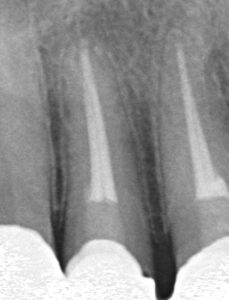

治療経過 左右ともクラウンを除去、土台のメタルコアーも除去。前医のガッタパーチャポイントも除去し、水酸化カルシウム製剤で根管通過を行う。

【左右ともに根尖病巣に水酸化カルシウム製剤が入っている】